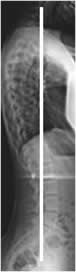

Desbalance sagital:

Se mide en la proyección lateral, determinando la distancia que existe entre la vertical que cruza por la mitad del cuerpo de C7 y la línea que pasa por el borde posterior superior de S1. (25, 26). (Fig 35).

Normalmente la distancia también es menor de 2 cm. Se habla de balance positivo cuando la distancia es mayor de 2 cm, por delante del sacro y negativo, cuando se localiza por detrás del sacro. (25, 26). (Fig 36 y 37).

Fig 36. Balance sagital patológico.

Rx lateral. La línea del borde posterior superior del sacro (Continua), se localiza por detrás de la línea cervical (Discontinua) y a una distancia mayor de 2 cm, por balance negativo.

Fig 37. Balance sagital patológico.

Rx lateral. La línea del borde posterior superior del sacro (Discontinua), se localiza por delante de la línea cervical (Continua) y a una distancia mayor de 2 cm, por balance positivo.